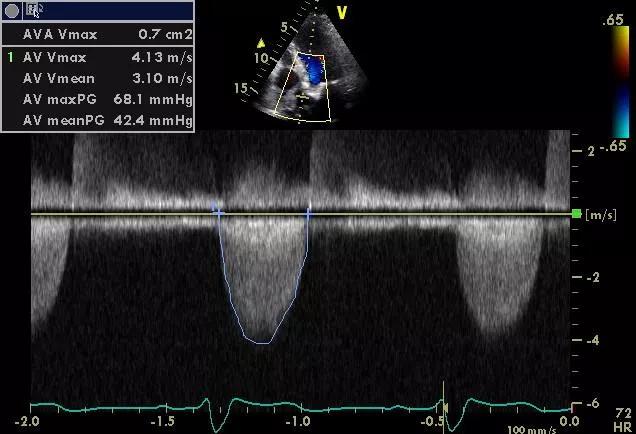

The new study, published in the Journal of the American Heart Association, was an observational cohort analysis of patients with severe symptomatic aortic stenosis who underwent SAVR at Cleveland Clinic from 2000 to 2015. Within this population, 172 patients were identified who had undergone mediastinal irradiation before developing aortic stenosis. This “XRT group” was matched 1:1 on the basis of age, sex, type and timing of SAVR, and aortic valve area with 172 SAVR patients with no history of mediastinal irradiation (comparison group).